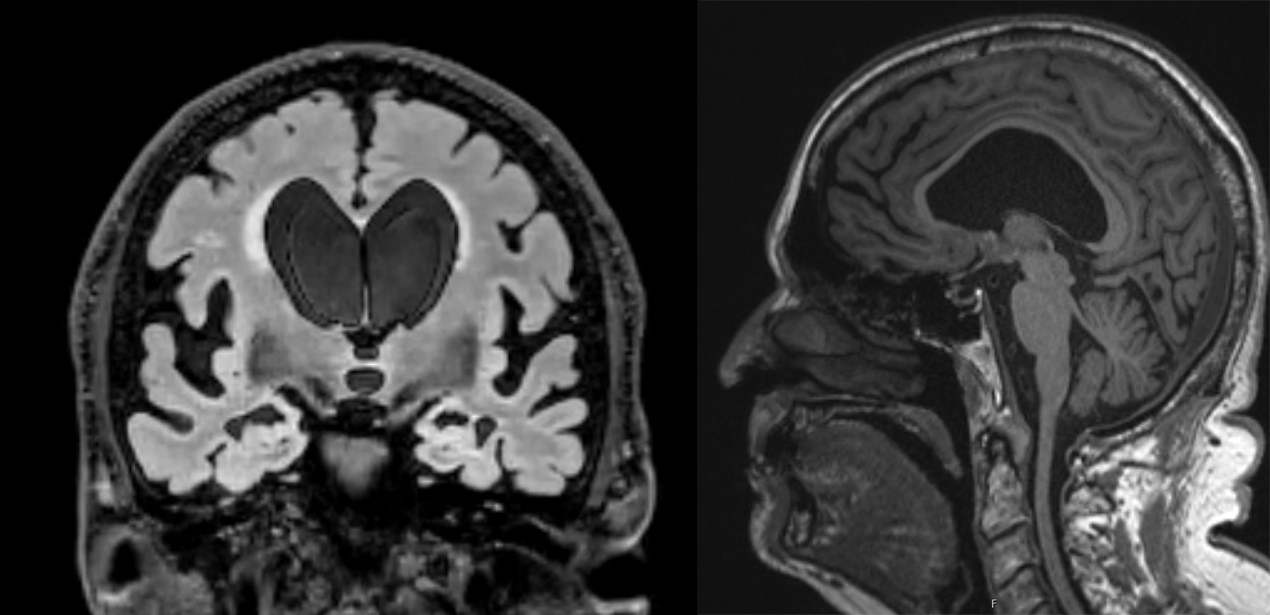

Brain scans showing expanded ventricles in the middle of the brain and evidence of disproportionately enlarged subarachnoid space hydrocephalus (DESH).

From the look of his scans, the ventricles in the middle of Mr. Nash’s brain had enlarged a significant amount. In hydrocephalus patients, this is typically caused by excess CSF pressure, which stretches and expands the ventricles over time. Theoretically, this could be the reason for NPH patients’ issues with walking and balance. Since the ventricles are closely tied to the corticospinal tract, which connects to the spine, the expanded ventricle could disrupt communication between the brain and the legs.

Mr. Nash’s imaging also showed evidence of disproportionately enlarged subarachnoid space hydrocephalus (DESH), where CSF is trapped and accumulates in the sulci (grooves or furrows of the brain), creating widening spaces that press on the brain. On scans, a space like this can look like brain shrinkage, which may have contributed to Mr. Nash’s earlier misdiagnosis. While not integral for an NPH diagnosis, DESH is one of the more specific diagnostic features of idiopathic NPH – it even plays a strong role in Japan’s clinical diagnostic guidelines.